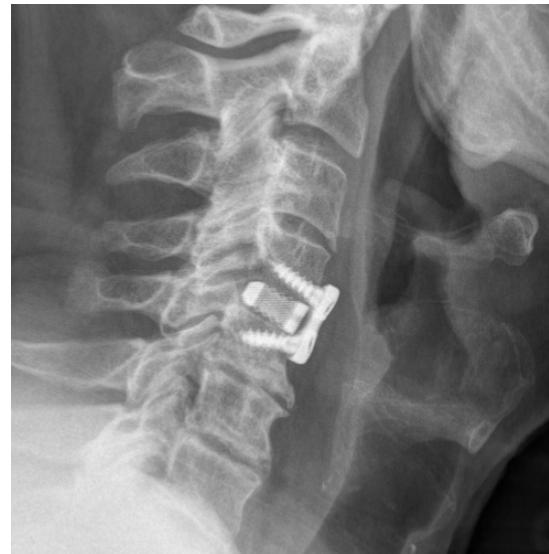

Imaging Examples:

Surgical Treatment - Anterior Cervical Discectomy and Fusion: